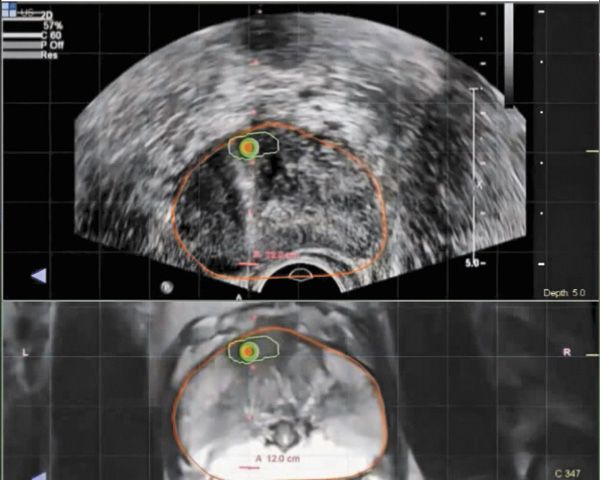

Fusion-guided prostate biopsy is performed at North Shore-LIJ School of Medicine using the UroNav system. Bottom screen shows a previously obtained MRI; green circle with red dot represents suspicious area. Top screen shows a real-time ultrasound, with red outline indicating the MRI that has been overlaid. Biopsy needle can be placed deep into the prostate to biopsy the top of the gland, which is not normally sampled during a standard 12-core biopsy.